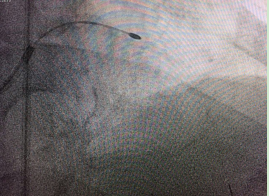

旋磨術(shù)手術(shù)中

入院后兩周,袁小蓉帶領(lǐng)冠脈介入團隊經(jīng)過精心準備后,對陳大爺施行了最先進的冠脈血管內(nèi)超聲檢查術(shù)+冠脈內(nèi)膜斑塊旋磨術(shù)。

術(shù)前,介入專家首先對陳大爺進行了冠脈血管內(nèi)超聲檢查,明確血管內(nèi)結(jié)構(gòu)以及鈣化病變位置和嚴重程度。然后將帶有鉆石顆粒的高速旋磨頭送入患者血管內(nèi)的鈣化部位,在醫(yī)生的精細操作下,位于血管內(nèi)的磨頭便以每分鐘10多萬次的轉(zhuǎn)速開始高速旋轉(zhuǎn),根據(jù)“差異性切割”(即只針對嚴重鈣化和纖維化的病變斑塊組織而不損傷正常組織)原理,將阻塞血管的動脈斑塊迅速磨成極其微小的顆粒,隨血液循環(huán)至血管遠端并通過毛細血管床吸收。經(jīng)過幾次旋磨后,阻塞血管腔的鈣化斑塊被逐漸消除,在進行球囊擴張之后,在兩支血管內(nèi)順利植入四枚支架,成功開通血管,手術(shù)時間總共用時1個多小時。